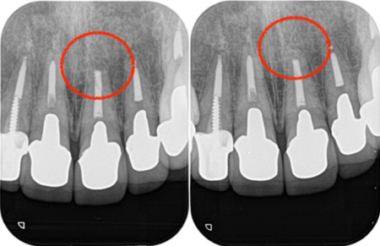

治療詳細レントゲン画像①|【症例】セラミック治療後に発症した根尖性歯周炎に対する歯根端切除術|目白マリア歯科

左:術前 右:術後

治療詳細レントゲン画像②|【症例】セラミック治療後に発症した根尖性歯周炎に対する歯根端切除術|目白マリア歯科

左:術後3ヶ月 右:術後1年